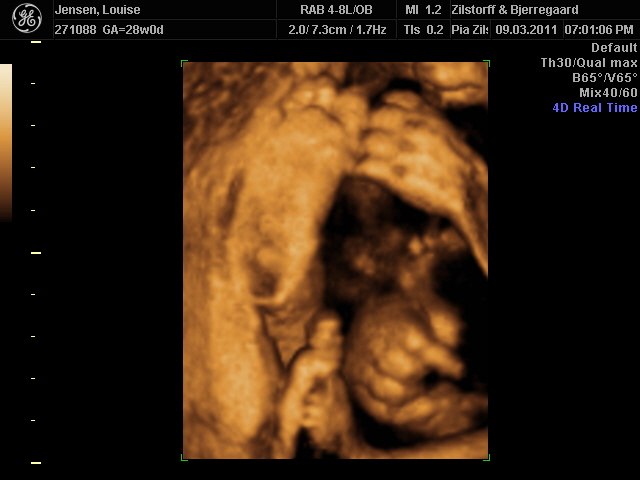

Jeg og kæresten var til 3D-scanning igår - sikke da en oplevelse  - det er da helt klart alle pengene værd ..

Hold da op en smækker lækker baby'boy der gemmer sig derinde i hulen, fy føj mor her fik tårere i øjne .. sikke da alt den kærliighed der væltede over mig .. suk suk

han ligner han far meget  - det er så vidunderligt hvad man dog kan se..

perfekt hjertelyd og vægten siger 1166 og er i uge 29 nu

Vedhæftede fotos (klik for at se i fuld størrelse)